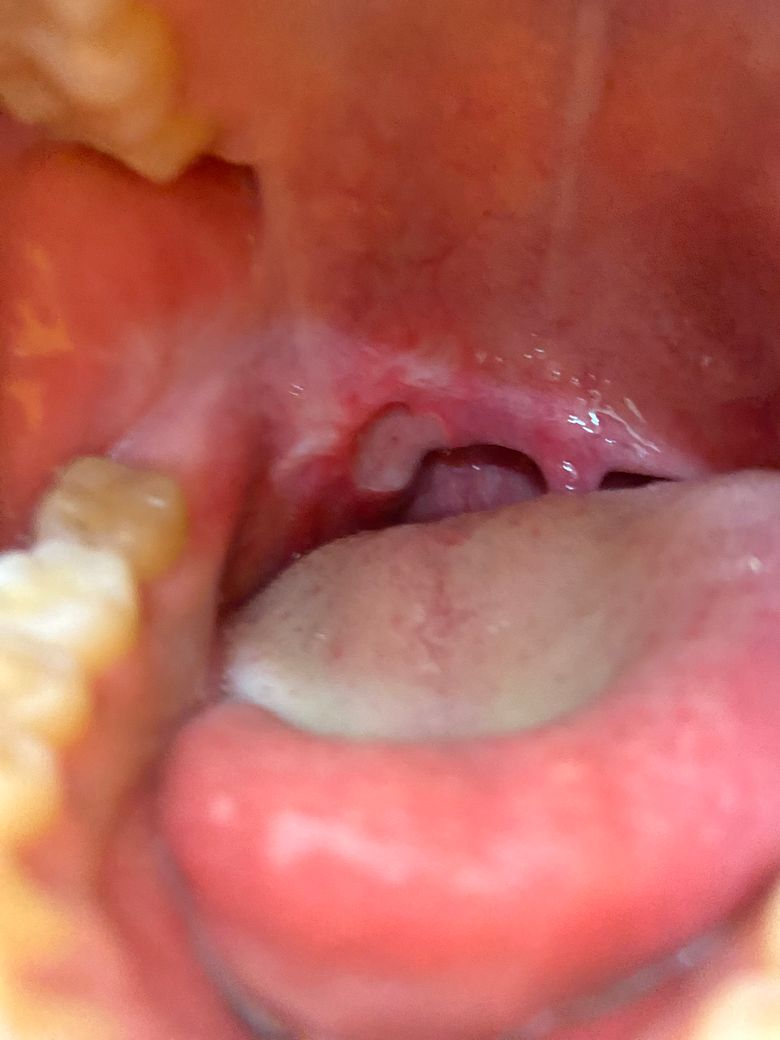

편고수술후 편도부위에 구내염같은게 생겼어요 재수술해야하나요?

3달전에 편도수술을 하고 잘지내고있었는데 갑자기 목쪽에 구내염같은게 생겨서 병원에 가보니 염즘이라고 약만 먹었는데 일주일이 지나도 났질않고 점점커지며 피까지 납니다 재수술을 해야할까요

• 1번 째 사진